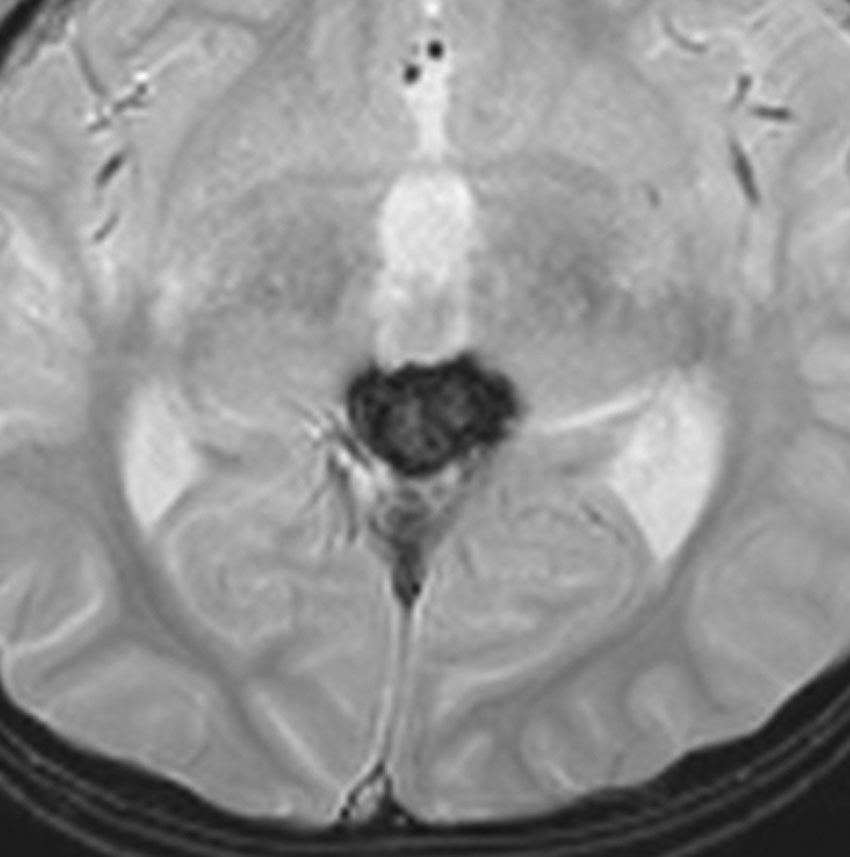

松果体芽腫グレード4の症例

水頭症で発症した6歳児で,4cmくらいある大きな松果体芽腫でした。大学病院で第3脳室開窓術と生検術をして,脳脊髄照射30グレイ(20分割),局所60グレイ(35分割)の放射線治療が行われました。さらにシスプラチンを基剤とした化学療法が3コース行われましたが,放射線で縮小した腫瘍は少し増大してしまいました。

放射線化学療法後の画像です。腫瘍境界は不明瞭(左)で,腫瘍内出血(中央)して,左の視床に浸潤しています。かなりリスクは高いのですが,これを開頭手術で全摘出しました(右),この時点で完全寛解 CR です。この後にさらに化学療法と幹細胞移植(PBSCT,大量化学療法)が加えられました。